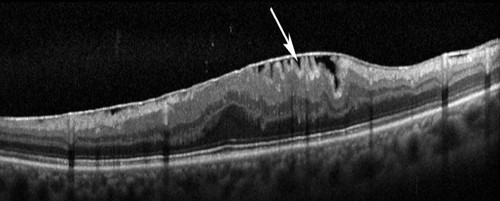

Tomografia de retina mostrando uma membrana na superfície da retina

O diagnóstico é feito através do mapeamento de retina (fundo de olho) e confirmado com tomografia da retina (OCT).